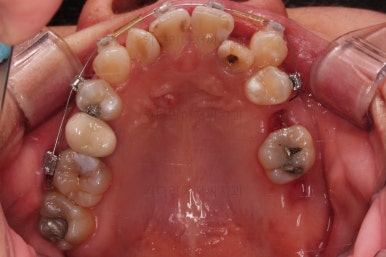

초진 시 입안의 모습입니다.

이미 썩어서 부러진 치아도 몇 개 보이고요.

많이 삐뚤어진 치아쪽은 양치가 힘들어 이미 많이 썩어 있는 상태에 덧니쪽은 잇몸도 많이 내려간 상태였습니다.

말그대로 교정치료 뿐만 아니라 전반적인 치료가 필요한 상황이었습니다.